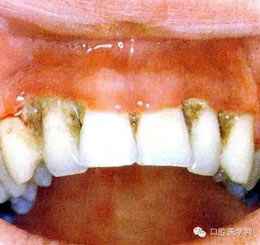

(四)壞死性齦炎:為局限的或普遍的潰瘍形成,牙間乳頭破壞,并伴有纖維蛋白性壞死。

(五)牙周炎:為牙周軟組織喪失及不規(guī)則骨破壞,可有明顯的疼痛。(早期)牙周炎軟組織損害呈火山口樣。